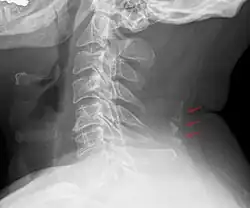

Neck

- Nodules in the posterior margin of the nuchal ligament form bone tissue in approximately 11% of males and 3–5% in females after the third decade of life, and may then be regarded to be sesamoid bones.[22]